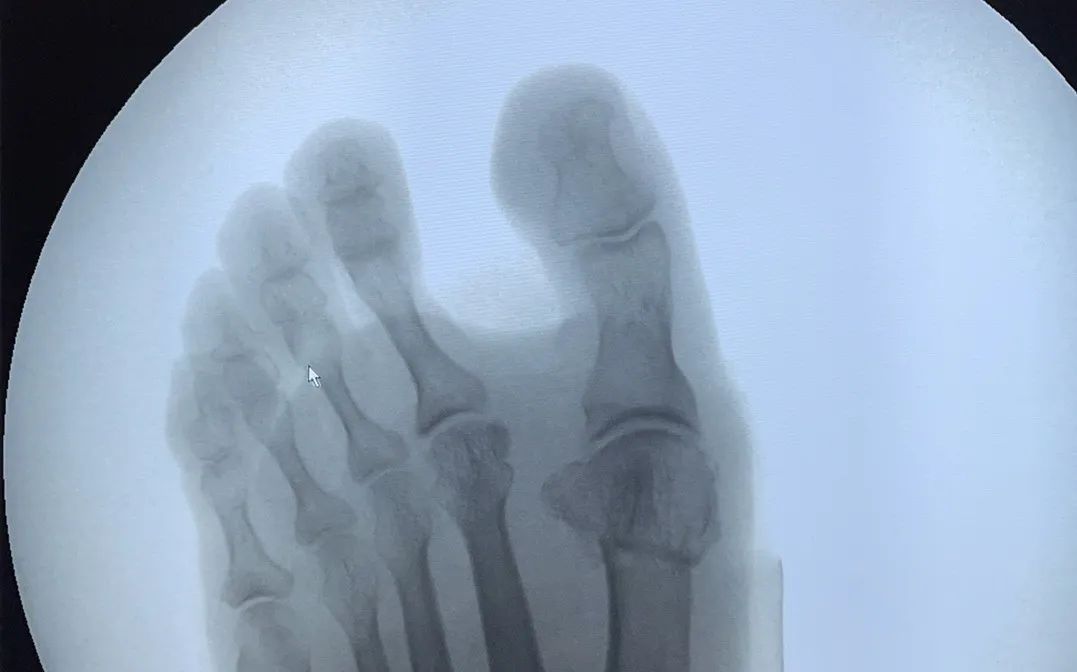

△患者手術(shù)前后比對

對于非手術(shù)干預(yù)無效或嚴(yán)重影響生活質(zhì)量的患者,可考慮手術(shù)干預(yù)。

微創(chuàng)矯形干預(yù)拇指外翻的優(yōu)勢

? 術(shù)后創(chuàng)口僅0.5-1cm

? 手術(shù)時(shí)間雙腳僅需30-40分鐘

? 術(shù)后即可穿戴矯正器

? 6小時(shí)候后可下地行走

? 6周后可正常穿鞋生活